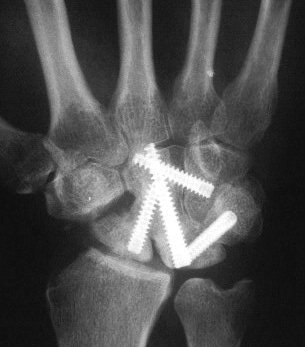

Carpal tunnel developed and progressively worsened, probably related to the palmar prominence of the lunate. The patient underwent carpal

tunnel release and midcarpal fusion and returned to heavy manual work.